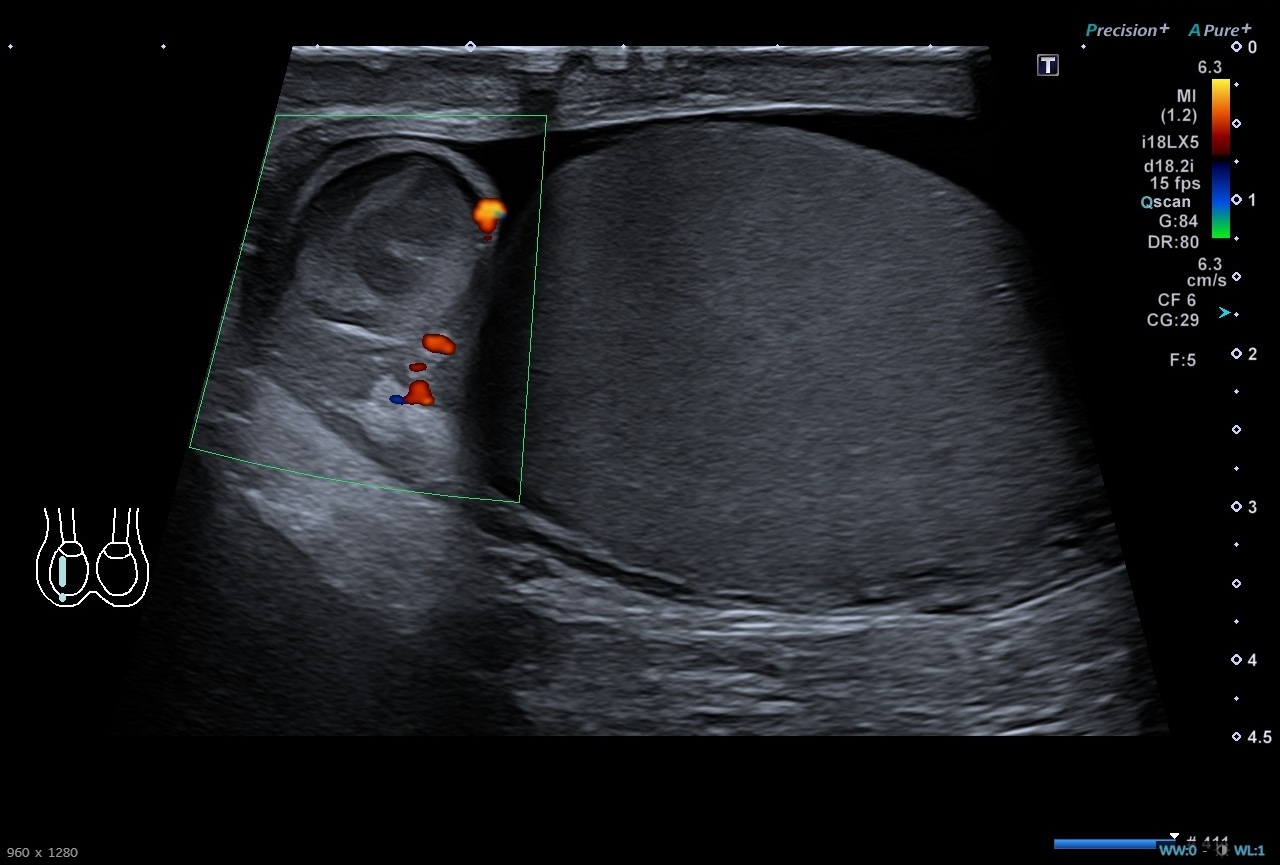

Pruebas complementarias: Sistemático de orina negativo. Ecografía escrotal: Testículos, epidídimos y cordones espermáticos de tamaño, morfología y ecogenicidad normales. Doppler normal en ambos testículos. Adyacente al polo superior del testículo derecho se identifica una estructura redondeada de unos 13 x 12 mms de ecogenicidad heterogénea, sin captación Doppler interna. Es sugestivo de torsión de hidátide de Morgagni, a correlacionar con evolución clínica. No hay datos de torsión testicular. Presencia de moderado hidrocele de aspecto reactivo.